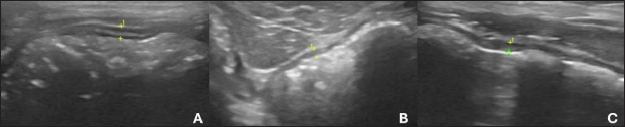

There is difficulty in scanning the colon due to the large amount of gas that is naturally present, plus the fecal material that is stored is an additive factor in the difficulty of evaluation (Larson and Biller, 2009). The transverse colon lies immediately caudally to the stomach and duodenum, while the descending branch can be found caudally and dorsally to the urinary bladder (Goggin et al., 2000). The segments of the colon are shown in Figure 2.

Fig. 2. Ultrasound images of the colon in healthy dogs. A, ascending colon; B, transverse colon; C, descending colon. All segments with wall thickness were measured using the ultrasound machine’s software cursor. An 8-MHz microconvex transducer was used, and longitudinal section images.